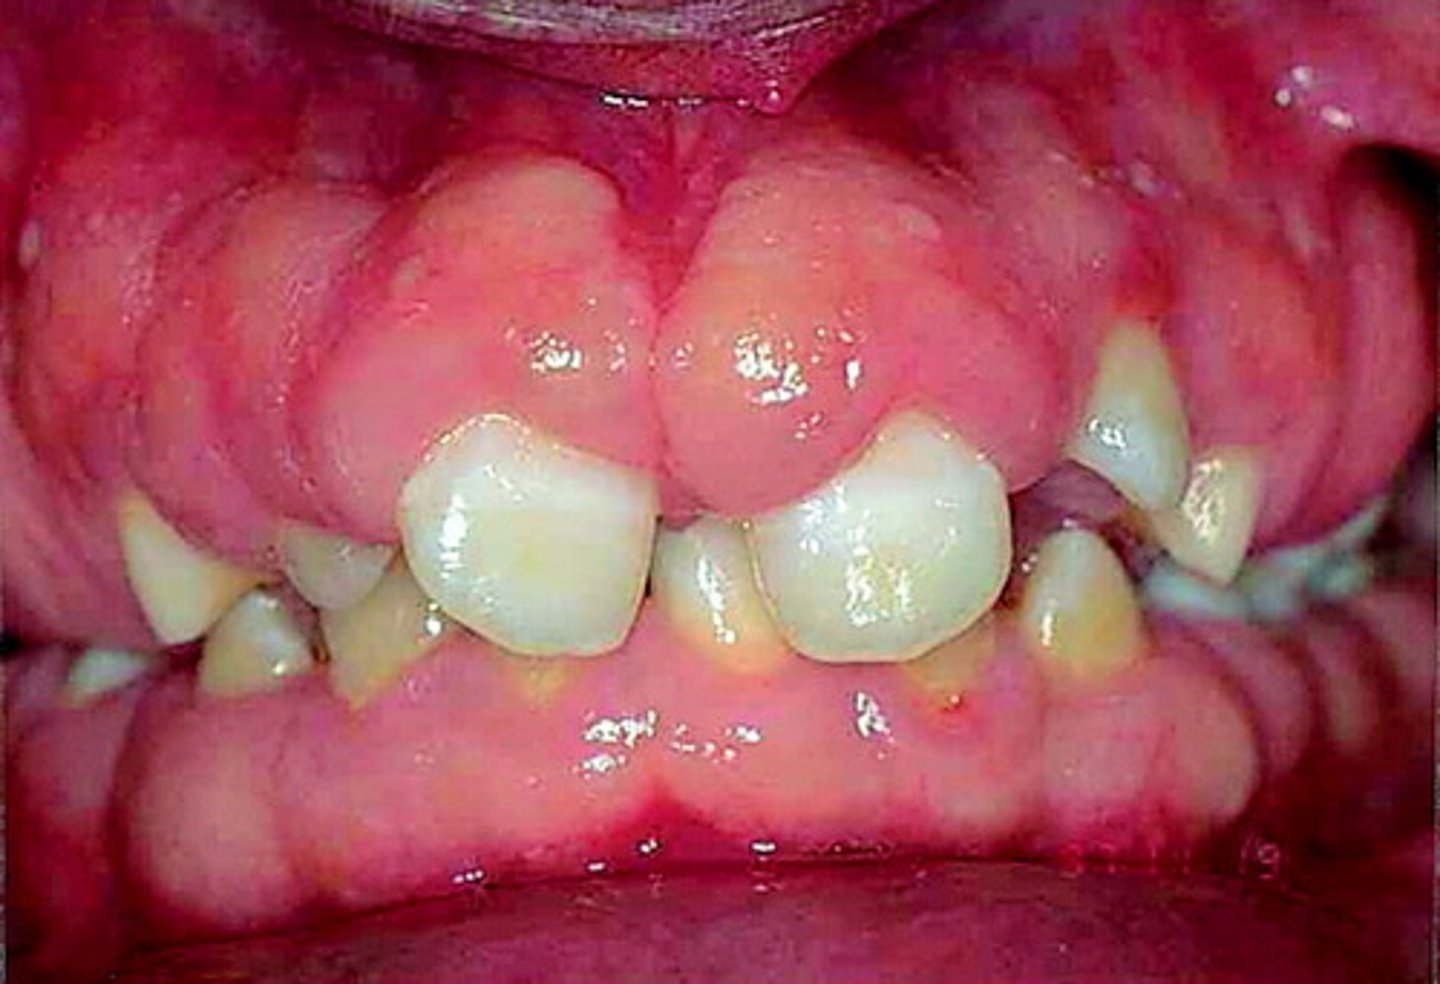

Oral features of Gingival fibromatosis

Gingival hypertrophy (firm, pale ,pink tissue)

Gingival fibromatosis